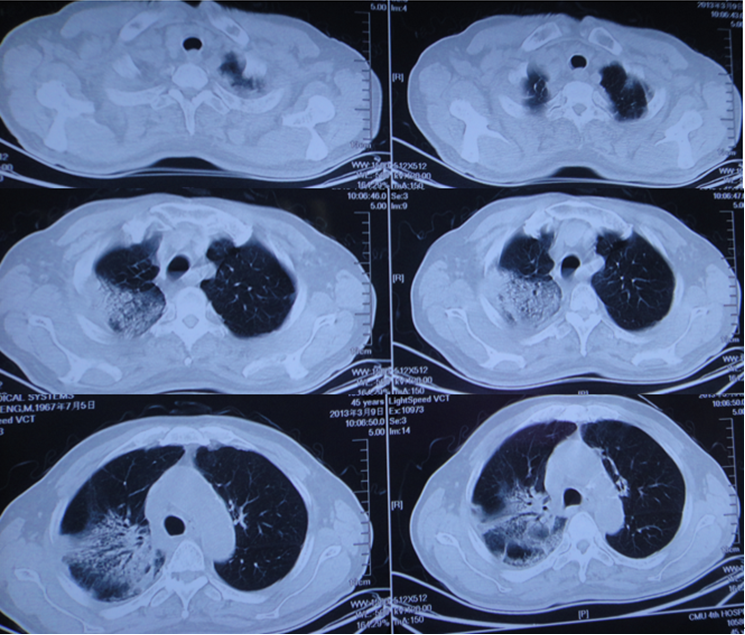

图6为HP患者的胸部CT,广泛的磨玻璃影,夹杂小叶中心结节。

图6  HP患者胸部CT

对于急性重型ILD,一定要做到早期识别、早期诊断和早期治疗。我们团队救治成功的病例基本上是在1周之内开始大剂量糖皮质激素治疗。这是我们近期收治的病例,有上呼吸道感染的前驱症状,胸部CT可见明显实变,磨玻璃影,小叶间隔增厚,患者快速进展至呼吸衰竭。

气管插管后完善病原学筛查,尽快给予皮质激素冲击治疗,1周后,患者胸部CT可见病变明显缓解,患者于第10天拔管,后续情况非常稳定。对此类患者,只有平安度过急性期,才有机会进行后续治疗,患者也才能获得良好的预后。